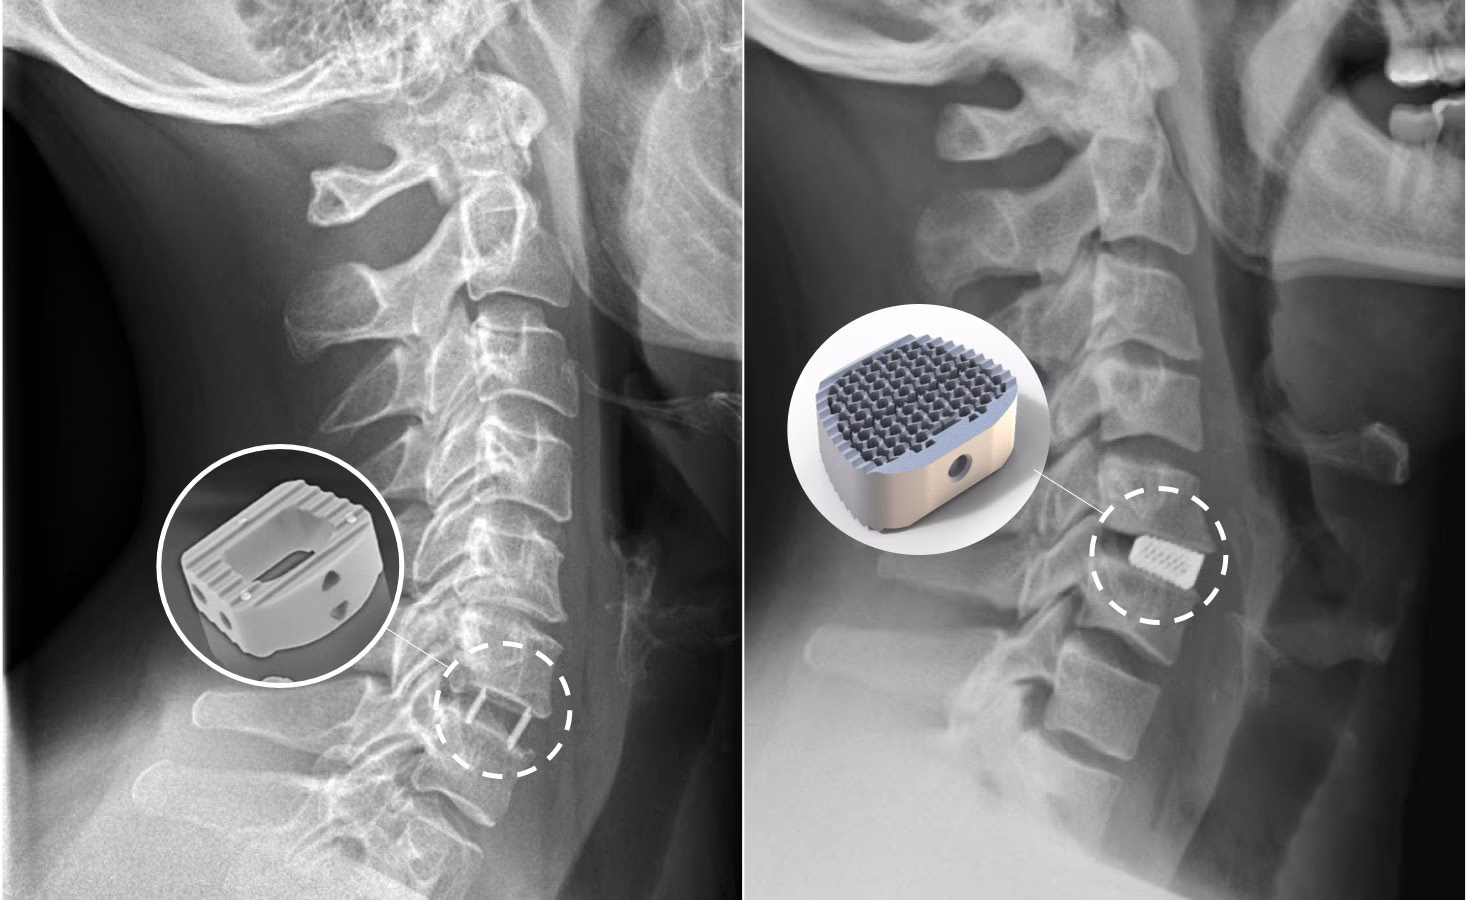

Det mest almindelige kirurgiske indgreb foretages fra forsiden af halsen. Kirurgen fjerner den beskadigede diskusskive (diskektomi) for at fjerne trykket på nerven. Herefter er der typisk to muligheder:

- Stivgørende operation (Fusion med cage): Efter diskusskiven er fjernet, indsættes et lille bur-lignende implantat (en 'cage'), ofte lavet af titanium eller PEEK-plast, fyldt med knoglemateriale. Dette får de to hvirvler til at vokse sammen over tid og skaber et stabilt segment.

- Indsættelse af diskusprotese: En kunstig diskusprotese indsættes for at erstatte den fjernede skive. Fordelen ved denne metode er, at den bevarer bevægeligheden i det pågældende nakkesegment.

Valget af operationstype afhænger af patientens alder, tilstandens omfang og kirurgens vurdering.